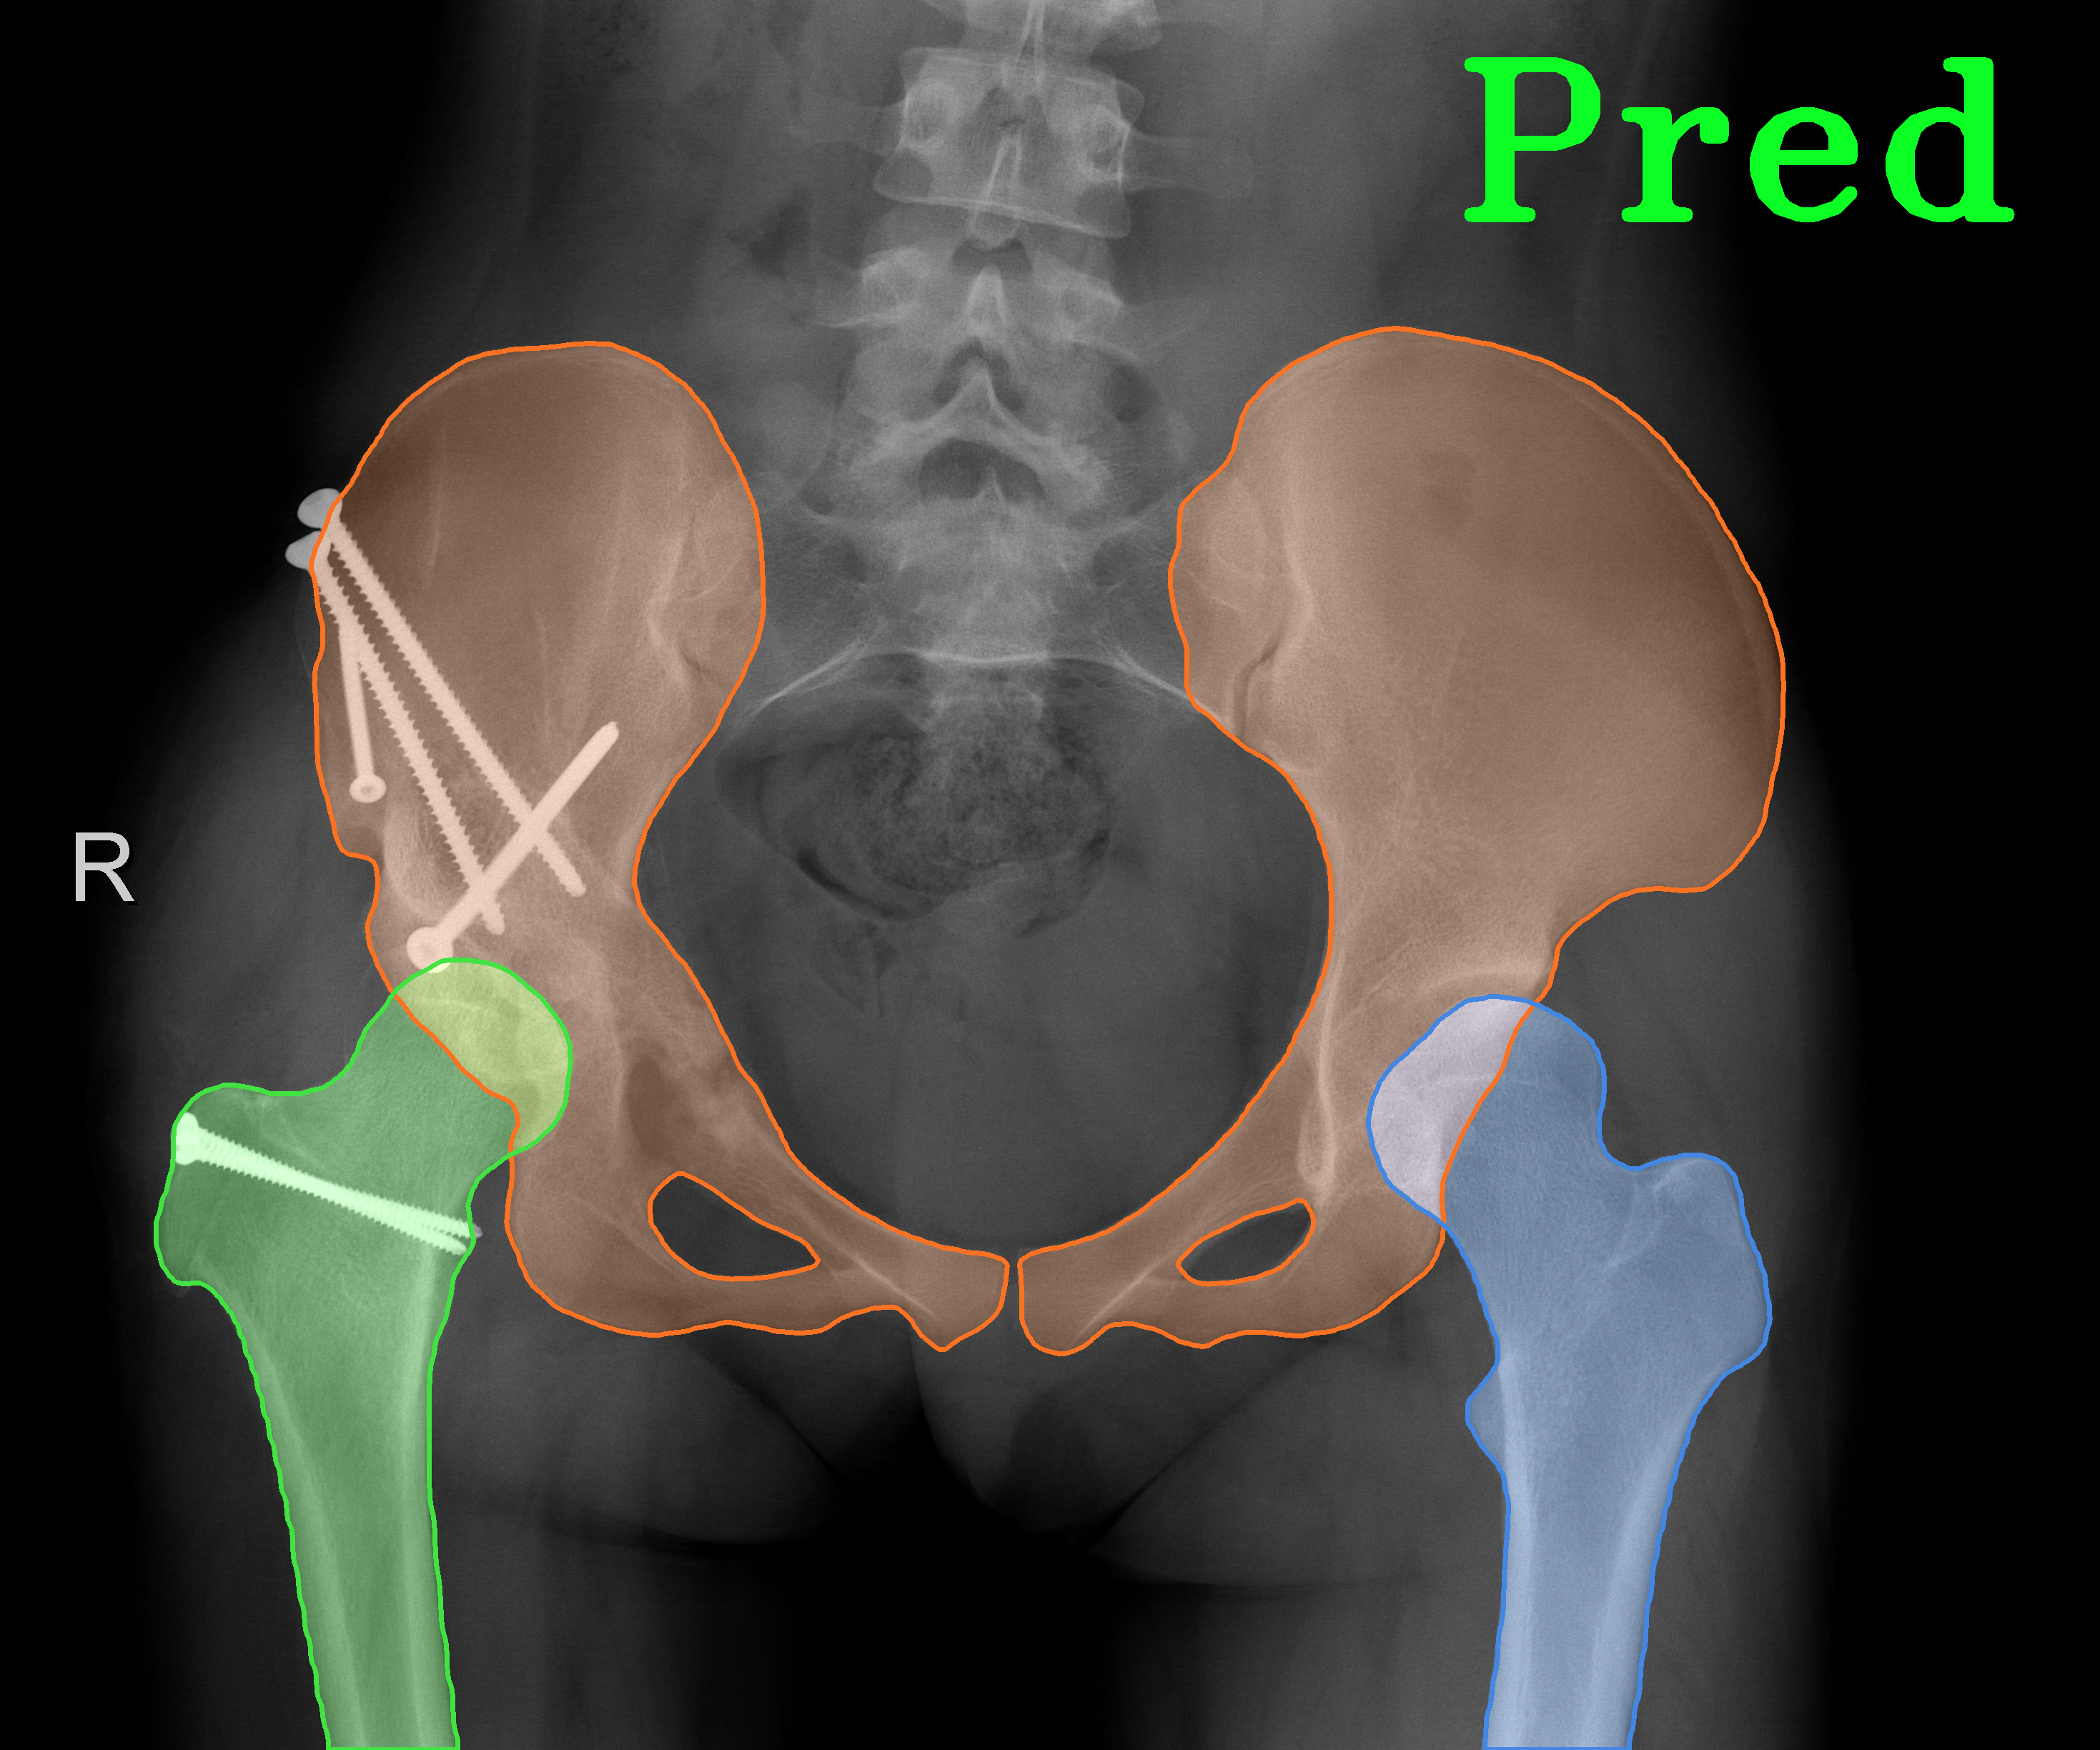

TransFuse is evaluated on both 2D and 3D datasets to demonstrate the effectiveness. As different medical image segmentation tasks serve different diagnosis or operative purposes, we follow the commonly used evaluation metrics for each of the segmentation tasks to quantitatively analyze the results. Selected visualization results of TransFuse-S are shown in Fig. 2.

Results of Hip Segmentation. Tab. 3 shows our results on hip segmentation task, which involves three human body parts: Pelvis, Left Femur (L-Femur) and Right Femur (R-Femur). Since the contour is more important in dianosis and THA preoperative planning, we use Hausdorff Distance (HD) and Average Surface Distance (ASD) to evaluate the prediction quality. Compared to the two advanced segmentation methods [33, 28], TransFuse-S performs the best on both metrics and reduces HD significantly (30% compared to HRNetV2 as well as 34% compared to Unet++ on average), indicating that our proposed method is able to capture finer structure and generates more precise contour.